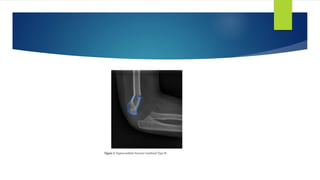

 A retrospective review was performed on all children sustaining a Gartland type II

and III supracondylar distal humerus fractures treated by closed reduction and

percutaneous pinning between January 2006 to December 2008 and January

2009 to December 2011.